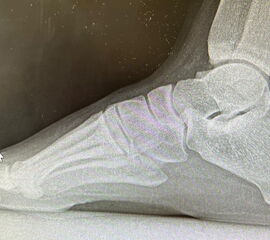

Abb.1 a-b: Beispiel einer noch offenen Wachstumsfuge im dorsalen Bereich des Calcaneus: (a) Alter 6 und (b) Alter 9 Jahre.

In der Regel bestehen aktive Wachstumsfugen bei Mädchen bis zum 12. und bei Jungen bis zum 14. Lebensjahr, mit Abweichungen von einem Jahr nach unten und nach oben. Präzise Informationen unter anderem darüber gibt das präoperative Röntgenbild (Abb. 2).